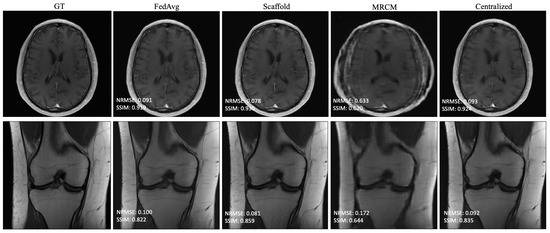

Based on the findings in Section 4.1, we selected 10 slices each from five different subjects, for a total of 50 local slices per client from the fastMRI dataset—this holds both for the i.i.d. and non-i.i.d. settings. The result of i.i.d. training is summarized in Table 2, which shows the average performance across all 10 sites that participated in training. For brevity, we report the average as we found that i.i.d. performance generally matched centralized training. All federated methods perform about the same or slightly better than centralized training in SSIM. The same is true with NRMSE. Centralized training and the federated unrolled optimization methods outperformed FL-MRCM. Figure 3 shows an example reconstruction for the i.i.d. case, comparing the ground-truth (GT) to FedAvg, Scaffold, FL-MRCM, and centralized training. Scaffold performed slightly better than FedAvg for this particular slice, and on-par with centralized, while FL-MRCM is poor, consistent with the results in Table 2.

The results of non-i.i.d. experiments are summarized in Table 3 and Table A1 in Appendix A for all fastMRI sites that participated in training. In this case, centralized and FedAvg perform about the same, while the adaptive federated algorithms typically perform slightly better. FL-MRCM is not competitive in this regime. Figure 4 shows example reconstructions of slices from two different sites. In this case, there is a clear qualitative and quantitative improvement between Scaffold and FedAvg, where the latter performs on par with centralized training.

Figure 3. Example reconstructions for knee PDFS 1.5T obtained in the i.i.d. client (knee PDFS 1.5T) scenario, and 240 communication rounds.

Bioengineering 10 00364 g003

Figure 4. Example reconstructions obtained in the non-i.i.d. client scenario with 240 communication rounds: (Top) Brain T1-POSTCON 3T, (Bottom) Knee PD 3T.

Bioengineering 10 00364 g004